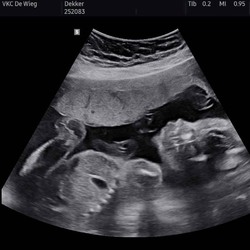

Eergisteren ben ik toch nog helemaal nagekeken door een verloskundige in het ziekenhuis waar ik werk. Ze is alles nagelopen, zowel de baby als de placenta en vruchtwater. Ook een eventuele vroeggeboorte is uitgesloten., alles wijst toch op een spier die erg overbelast is door teveel doen